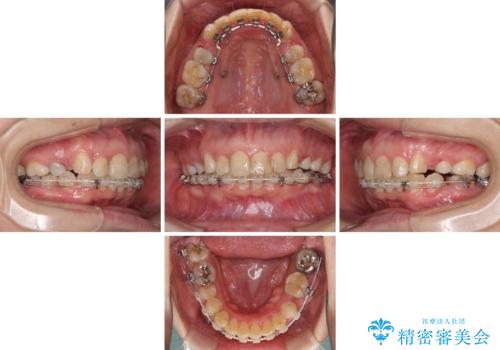

咬合力が非常に強く、スペースがなかなか閉じなかったことと、上下の正中が著しくずれてきてしまったため、下顎左側小臼歯を途中抜歯することとなりました。

歯の動きが鈍く、矯正治療だけで4年以上の期間を要することとなりました。

矯正治療後は、気になっていた銀歯を全てセラミックとし、きれいな口元に仕上げることができました。